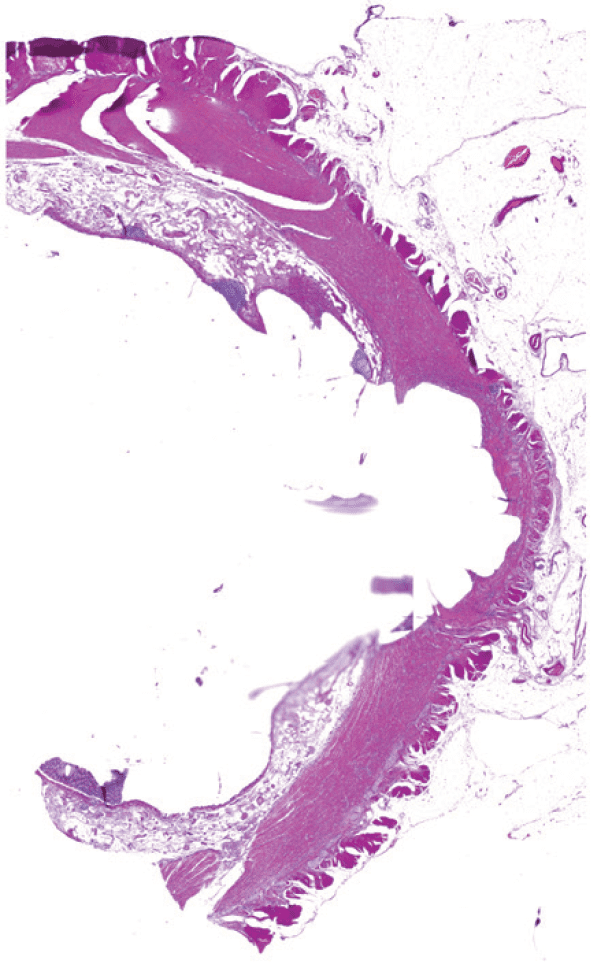

Representative images of H&E stained colorectal tumour showing spatial enrichment using Laser Microdissection (LMD).

(1) Prior to dissection

(2) Areas of interest annotated

(3) Tissues dissected

Figure 1: (1) Patient sample prior to dissection under the LMD. (2) Patient sample with tumour regions (red) and adjacent normal tissues (green) annotated to be microdissected. (3) Patient sample after all tissues of interest were dissected and collected into a 0.6 mL tube cap, with muscular/ adipose tissues remaining in the section. Magnification 2.5x.

Laser microdissected samples were captured with cut areas of approximately 100 × 106 μm2 for ~ 20μg of protein from colorectal cancer and normal adjacent samples (Figure 1). Digested samples were purified using StageTips, then reconstituted in 0.1% FA.